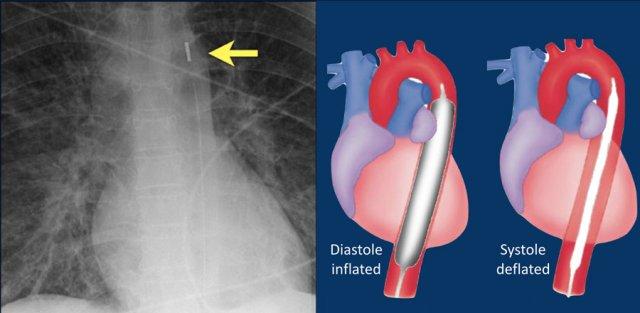

Bóng đối xung trong động mạch chủ

Bóng đối xung trong động mạch chủ (IABP) là một thiết bị cơ học giúp tăng cường tưới máu oxy cho cơ tim và gián tiếp làm tăng cung lượng tim thông qua cơ chế giảm hậu tải.

Thiết bị bao gồm một bóng polyurethane hình trụ được đặt trong động mạch chủ, cách động mạch dưới đòn trái khoảng 2 cm.

Bóng được bơm phồng và xẹp theo cơ chế đối xung, nghĩa là bóng chủ động xẹp trong thì tâm thu và phồng trong thì tâm trương.

Sự xẹp bóng trong thì tâm thu làm giảm hậu tải thông qua hiệu ứng chân không, từ đó gián tiếp làm tăng lưu lượng máu xuôi chiều từ tim.

Sự phồng bóng trong thì tâm trương làm tăng lưu lượng máu đến các động mạch vành thông qua dòng chảy ngược chiều.

Sự kết hợp của các cơ chế này giúp giảm nhu cầu oxy của cơ tim đồng thời tăng cung cấp oxy cho cơ tim (tài liệu tham khảo).